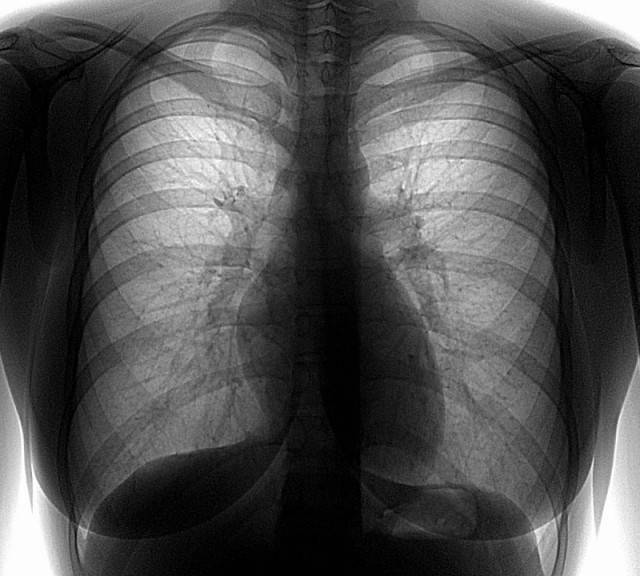

Клиника Скоромед предлагает пройти платную флюорографию на современном оборудовании. Наши филиалы имеют все необходимое для проведения оперативной и качественной рентгенодиагностики. Многим людям периодически нужно быстро сделать флюорографию для медицинского осмотра, продления санитарной книжки, но в государственных учреждениях приходится записываться с самого утра и выстаивать длинную очередь. Наверняка это не входит в ваши планы, особенно если рабочий график расписан по минутам. В филиалах нашей клиники вы за считанные минуты сможете сделать платно флюорографию даже в выходные дни.

Современное оборудование (флюорограф малодозовый цифровой ПроСкан) соответствует мировым стандартам качества и безопасности. Рентгенодиагностика проходит с минимальной лучевой нагрузкой, что позволяет считать флюорографию безопасным и высокоинформативным исследованием, которое применяется в качестве основного скринингового метода при туберкулезе легких.

Плановое исследование назначается всем людям один раз в 12 месяцев. Регулярная диагностика позволяет выявлять скрыто протекающие патологии легких, включая туберкулез, пневмокониозы, доброкачественные и злокачественные новообразования.